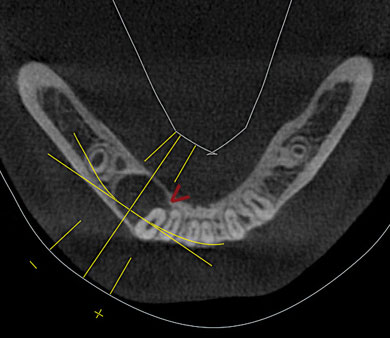

Gefahr der Nervverletzung bei der Weisheitszahnentfernung

Die Gefahr von Nervverletzungen können wir dadurch erheblich reduzieren!